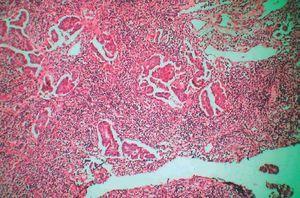

El estudio histopatológico de una de las lesiones cutáneas puso de manifiesto, a nivel de la dermis superficial y media, vasos linfáticos dilatados ocupados por una proliferación neoplásica de estirpe epitelial constituida por células cúbicas de citoplasma eosinófilo y gran núcleo redondeado con nucleolo prominente, que focalmente presentaba una disposición papilar. Llamaba la atención la elevación de la epidermis suprayacente (fig. 3).

Figura 3. Hematoxilina-eosina, x400.

El estudio de la adenopatía de la región inguinal derecha evidenció un ganglio linfático que tenía los senos con focos de una tumoración epitelial con patrón papilar (fig. 4).

Figura 4. Hematoxilina-eosina, x200.

Las lesiones de apariencia vesiculosa en el seno de metástasis cutáneas ha recibido distintas denominaciones en la literatura: lesiones herpetiformes3, zosteriformes5,6 o tipo linfangioma4,7,8. No está claro a qué sustrato histológico se debe el aspecto vesiculoso de las lesiones. En nuestro caso parece causado por la infiltración y obstrucción de los vasos linfáticos por émbolos tumorales a nivel de la dermis papilar, elevando la epidermis suprayacente respecto al nivel general de la piel (fig. 3).